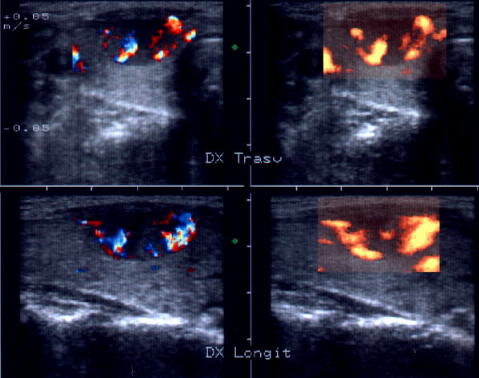

ecocolordoppler si powerdoppler- acelasi nodul

Vascularizatie interna, mai evidenta in powerdoppler.

Acelasi caz. La doppler color - vascularizatie interna, mai evidenta in powerdoppler.